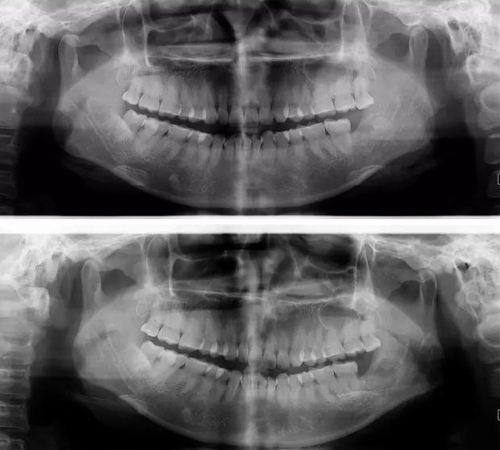

拔牙斷根的去與留?

下面看一個病例,患者,女,30歲,因左下頜智齒嵌塞食物后疼痛,至當(dāng)?shù)匮揽平o予拔除,但術(shù)后1個半月,患者自覺拔牙區(qū)一直隱隱疼痛,時輕時重,遂來診。檢查發(fā)現(xiàn),拔牙創(chuàng)口一直未愈合,未見明顯腫脹,拍片發(fā)現(xiàn),拔牙窩內(nèi)顯示高密度斷根影

像,該斷根臨近下頜神經(jīng)管,同時發(fā)現(xiàn)第二磨牙遠中有兩塊高密度影像,疑似殘留骨片或牙片,應(yīng)該是引起疼痛的原因,經(jīng)與患者溝通,采納建議,進行二次拔牙。